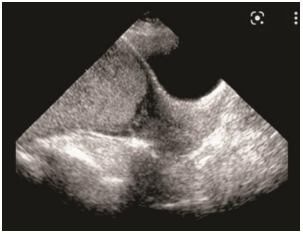

Mulher, 38a, G3P2C2A0, idade gestacional de 28 semanas e 5 dias (E₈), refere sangramento vaginal vermelho vivo em pequena quantidade há dois dias. Nega contrações, relação sexual ou esforço físico. Refere boa movimentação fetal. Nega perda de líquido por via vaginal. Exame físico: altura=1,71m; peso=85,5Kg; PA=122x72mmHg; FC=88bpm; altura uterina=27cm; batimentos cardíacos fetais=148bpm; dinâmica uterina=ausente; movimentos fetais=presentes. Especular=presença de pequena quantidade de sangue coletada em fundo de saco vaginal, sem sangramento ativo, colo aparentemente impérvio e sem lesões. Toque vaginal=não realizado. Solicitada ultrassonografia obstétrica, que apresenta a seguinte imagem.

A HIPÓTESE DIAGNÓSTICA É: